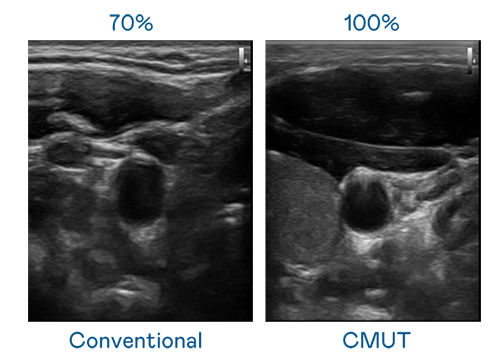

CMUT 技术是一种用电容式微机电元件来产生超音波讯号的技术。与传统 PZT 压电式技术相比,CMUT 频宽增加 30%,更宽频的超音波讯号让影像解析度大幅提升,是实现高影像品质医疗超音波扫描、促进精准医疗发展的关键技术。

大频宽带来超清晰影像

超音波影像的解析度高低,首先取决于探头能发出的讯号频宽。hth·华体 CMUT 可提供高清晰的超音波讯号,提供高频宽、高灵敏度、影像纹理细节更高的超音波影像,协助医护人员缩短影像判读时间及利用精准的医疗影像进行诊断。